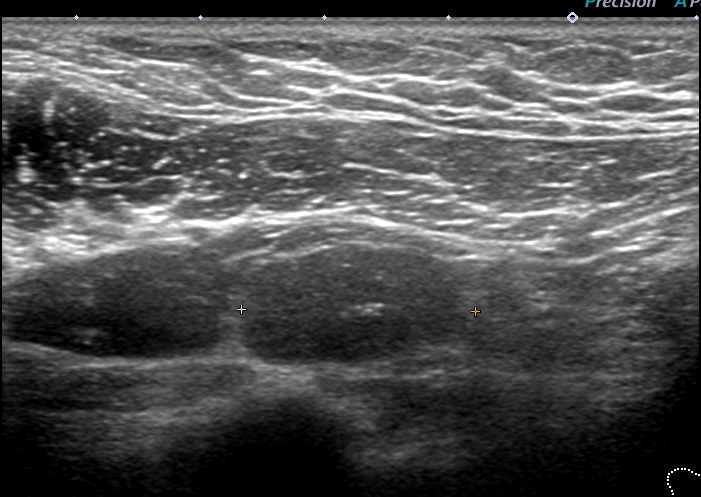

リンパ節の形態を失って「節外浸潤」している

♯そもそも、この大きさ(1.5cm)の細胞診を外していること自体、手技的に「不合格」ですね。

レベル2リンパ節 これが一番大きい 2㎝

形はリンパ節の形をしており「節外」では(画像上)なさそう。